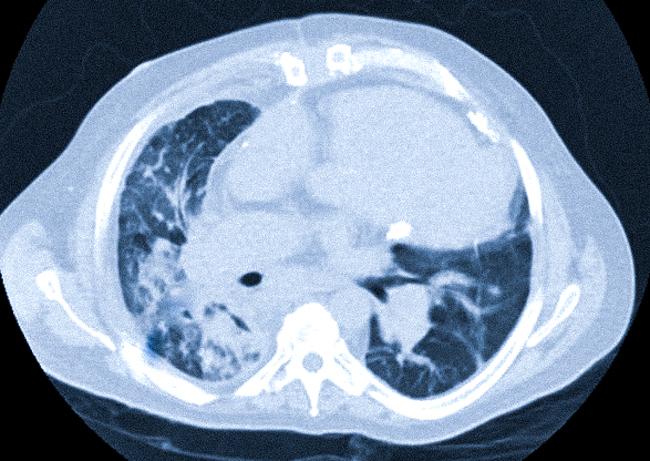

В течение нескольких недель перед госпитализацией пациент начал испытывать нарастающую общую слабость, продуктивный кашель и одышку. Установить причину ухудшающегося состояния удалось быстро: согласно КТ от 28.11.19, был выявлен полный ателектаз левого легкого.

Данные КТ от 30.11.19 превзошли наши ожидания и невероятно обрадовали пациента и его родственников: было зафиксировано восстановление воздушности левого лёгкого, лёгкое расправилось, от опухоли в области левого главного бронха остался лишь небольшой компонент по его стенке. Уже 04.12.19 пациенту была начата химиотерапия по схеме FOLFIRI + панитумумаб, а 07.12.19 пациент был выписан.

Пациент и его семья покинули нашу клинику с совершенно иным состоянием духа по сравнению с моментом поступления, с новыми перспективами и пониманием того, что возможности для их лечения далеко не исчерпаны, несмотря на то что в последнее полугодие им внушали обратное. Описание КТ-снимков: слева — КТ от 28.11.19: полный ателектаз левого лёгкого; справа — КТ от 30.11.19: восстановление воздушности левого лёгкого.